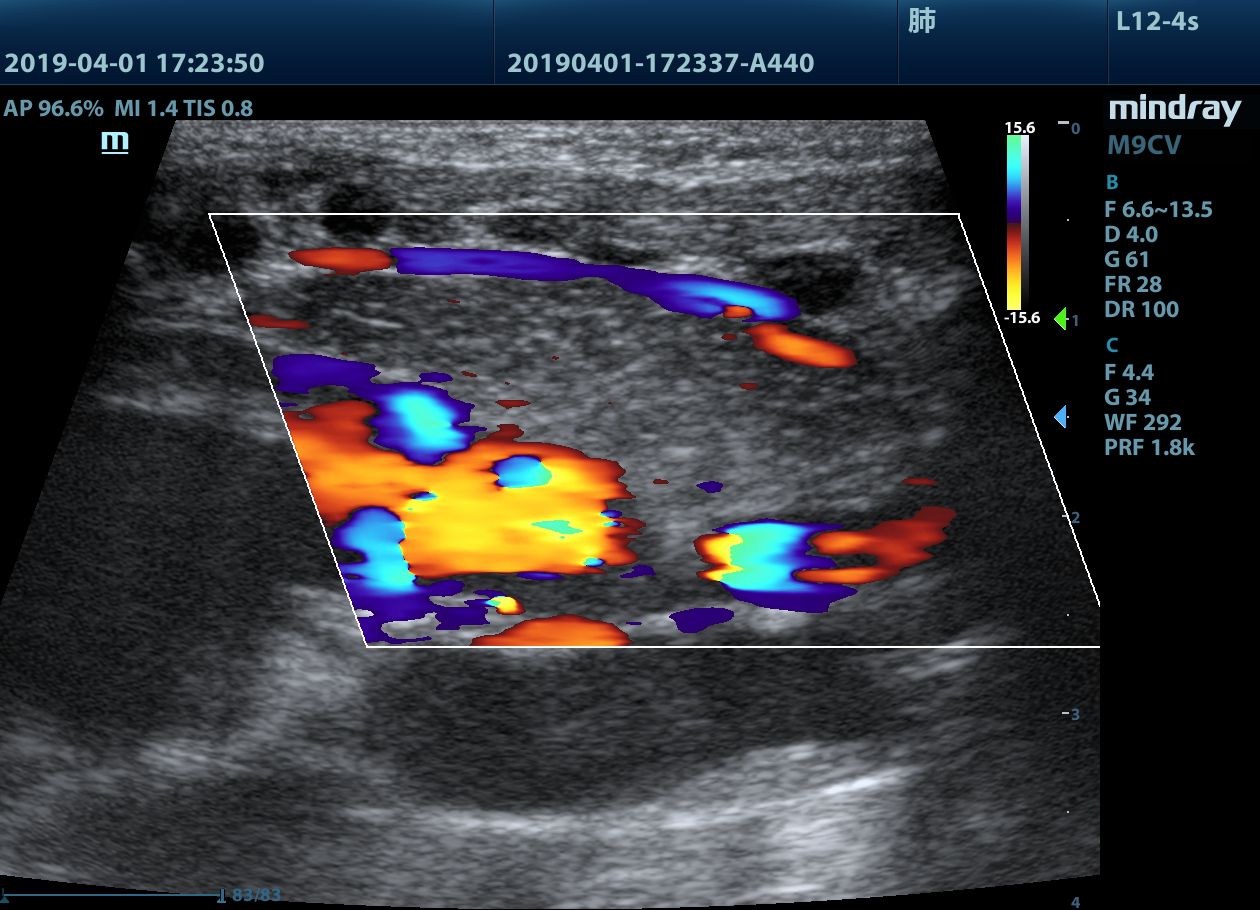

根据可视化的图标选择不同的临床应用